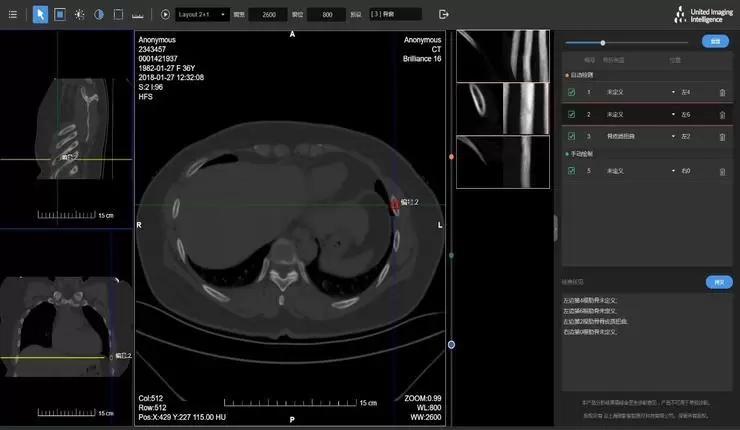

据联影智能的产品简介显示,此次获批的CT骨折智能分析系统具备“精准肋骨定位,秒级骨折检出,直观提示病灶”等一系列特点,以高敏感性辅助医生快速、高效、精准地完成肋骨的诊断,避免错诊和漏诊。其主要功能点为:

基于深度学习方法,自动完成肋骨定位、计数与标注,帮助医生“数肋骨”;

秒级完成全部检测流程,精准肋骨定位并提示肋骨骨折位置;

准确区分真实骨折与运动伪影、肋软骨、肋骨病变等假阳性情况;

支持半边重建、扫描视野不全、肋骨粘连、肋骨断裂/部分缺失等异常影像检测。

uAI 肋骨骨折智能分析系统

此外,系统可对工作流进行优化——提供三维重建(MPR、VR、MIP、MinIP)、动态展示、独立分部位展示、最佳视角、高危提醒等功能,协助医生快速准确定位和复核病灶,支持病灶标记图像一键回传PACS,自动生成不同模板的结构化报告。